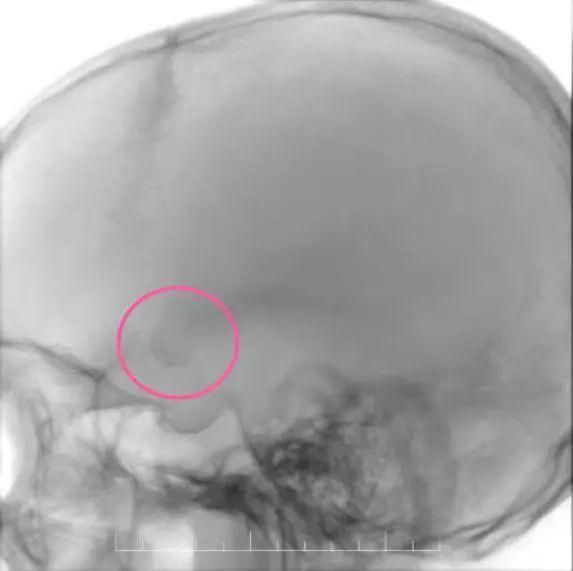

肖奶奶75岁,因“反复头晕伴行走不稳3月余,加重1周”入院。颈动脉彩超及DSA显示右侧颈内动脉C1段次全闭塞(狭窄率>90%),随时可能完全闭塞导致大面积脑梗死!

神经内科介入团队当机立断行右侧颈内动脉球囊扩张+支架植入术。术后血流恢复通畅,肖奶奶的头晕症状显著改善,行走稳定性明显提高。

▲肖奶奶右侧颈总动脉造影:术后颈内C1段狭窄段明显改善